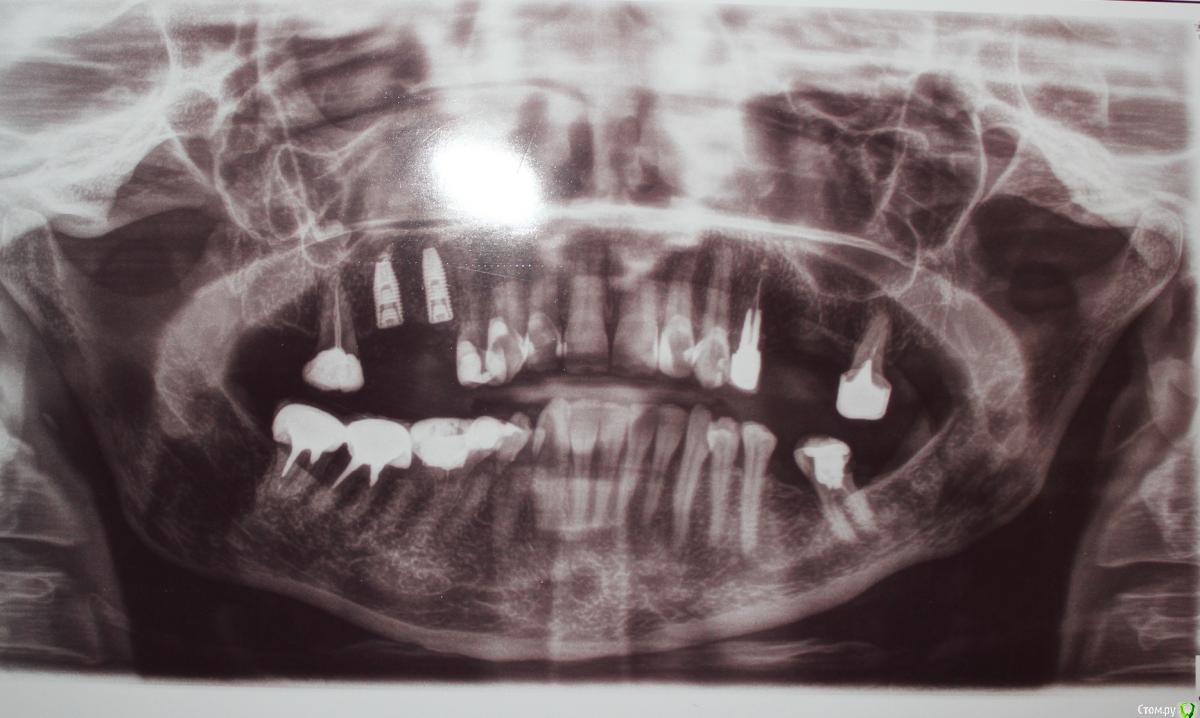

Patient_Nobel Опубликовано 18 мая, 2019 Поделиться Опубликовано 18 мая, 2019 Здравствуйте, форумчане!Были установлены два импланта Nobel. После операции сделали панорамный снимок. Дома посмотрела и расстроилась - один из имплантов установлен очень близко к зубу.Как я вижу, то нет места для установления коронки.Что это? Ошибка хирурга? или что-то можно сделать в такой ситуации? Ведь имплант уже не переставить(((( Ссылка на комментарий

kramer Опубликовано 18 мая, 2019 Поделиться Опубликовано 18 мая, 2019 Нормально там всё 1 Ссылка на комментарий

Большой Зеленый Опубликовано 18 мая, 2019 Поделиться Опубликовано 18 мая, 2019 Все отлично! Просто небольшое искажение .Это просто такой снимок ) Спите спокойно 1 Ссылка на комментарий